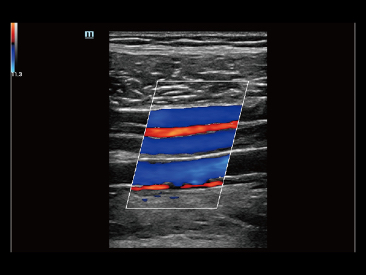

Oltre alla qualit├Ā delle immagini di livello eccellente, Resona 7 migliora anche le capacit├Ā di ricerca clinica il rivoluzionario V Flow per la valutazione emodinamica vascolare, e l'acquisizione piani pi├╣ intelligente dal set di dati 3D per la diagnosi del sistema nervoso centrale fetale. Combinando il pi├╣ intuitivo funzionamento multi-touch basato su gesti e tutte le caratteristiche cliniche essenziali, Resona 7 sta veramente portando nuove tendenze nellŌĆÖinnovazione dellŌĆÖecografia.